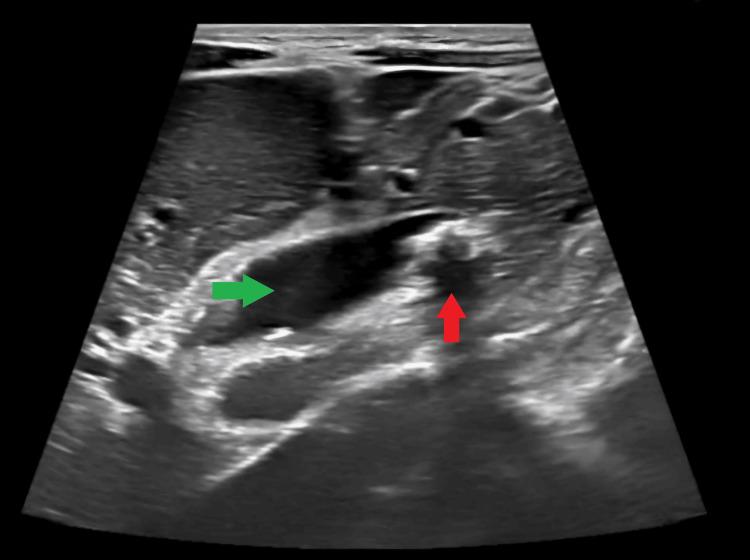

A contracted or "vanishing" gallbladder is a condition characterized by severe atrophy or fibrosis of the gallbladder, often resulting from chronic inflammation, recurrent cholecystitis, gallstone disease, or metabolic disorders such as diabetes and chronic alcohol use. The etiopathogenesis involves progressive fibrosis due to persistent biliary obstruction, chronic infection, or impaired blood flow, particularly in patients with liver cirrhosis. While the exact incidence remains unclear, it is more prevalent in individuals with long-standing hepatobiliary diseases or metabolic syndromes. Common symptoms include severe right upper quadrant pain, jaundice, nausea, vomiting, and signs of obstructive jaundice, such as dark urine and pale stools. Diagnostic investigations typically involve ultrasound, contrast-enhanced computed tomography (CECT), magnetic resonance cholangiopancreatography (MRCP), and endoscopic retrograde cholangiopancreatography (ERCP) to assess biliary obstruction, liver pathology, and gallbladder morphology. Treatment requires a multidisciplinary approach, including initial ERCP for biliary decompression, followed by surgical intervention (laparoscopic or open cholecystectomy), with conversion to open surgery often necessary due to dense adhesions and fibrosis. Postoperative care focuses on managing comorbidities, preventing complications, and long-term monitoring of liver health. This case report presents the challenging management of a 34-year-old male with a history of diabetes mellitus, chronic alcohol use, and liver cirrhosis, who presented with severe right upper quadrant pain, jaundice, and ascites. Initial evaluation revealed cholangitis, calculous cholecystitis with choledocholithiasis, and imaging findings consistent with liver cirrhosis. The patient underwent ERCP for biliary stenting and sludge extraction, followed by an attempted laparoscopic cholecystectomy. Intraoperatively, dense adhesions and fibrosis obscured the gallbladder, confirming a contracted or "vanishing" gallbladder, prompting conversion to an open procedure. The case highlights the diagnostic complexities of contracted gallbladders, which often result from chronic inflammation, fibrosis, or metabolic disorders. Preoperative imaging, including ultrasound and MRCP, played a critical role in identifying biliary obstruction and liver pathology. However, intraoperative findings necessitated adaptive surgical decision-making to mitigate risks such as bile duct injury or hemorrhage. The patient's multiple comorbidities further complicated management, emphasizing the need for a multidisciplinary approach involving gastroenterologists, surgeons, and hepatologists. Postoperative recovery was closely monitored for complications, including infection and bile leaks. The patient was discharged with follow-up care focusing on liver health, diabetes management, and alcohol cessation. This report underscores the importance of thorough preoperative assessment, flexibility in surgical technique, and collaborative care in optimizing outcomes for patients with complex gallbladder pathology. Future research should explore long-term outcomes and improved imaging techniques to enhance surgical planning for such challenging cases.